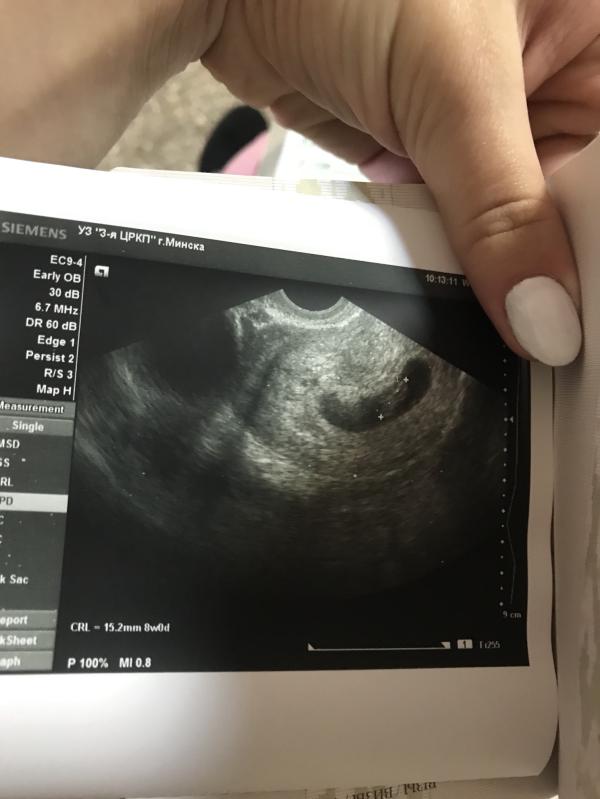

Была киста на правом яичнике, обнаружили на УЗИ в 8 недель, размер 1,3×1,2 см. Наблюдали в динамике. В итоге экстренно удаляли на 23-й неделе (достигла размеров 9×10 см, перекрут, риск разрыва, появился кровоток и сОлидный компонент). Операция полосная. Через месяц пришла плохая гистология. Беременность сохранили. Сыну уже 2,4